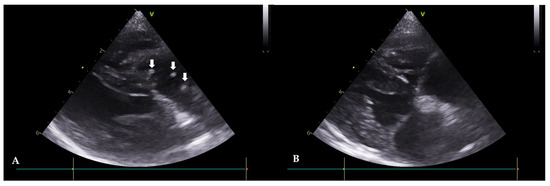

Figure 3. Echocardiograms of Case 2 before (A) and after (B) HW removal (right parasternal, short axis view). (A): Before the procedure, HWs are observed in the right atrium and ventricle (white arrows). (B): After the procedure, HWs are not observed.

A 13-year-old, spayed, female Yorkshire terrier, weighing 3.72 kg, was referred with symptoms of abdominal distension, anorexia, and tachypnea. In radiography, there was evidence of an enlargement of the left and right heart chambers, a reverse D heart shape (VHS 10.4), and a decreased visibility of the diaphragmatic line in the upper abdomen. The echocardiogram revealed HWs inside the right atrium, and severe tricuspid regurgitation was confirmed (Figure 3A). Mitral valve lesions were not identified. Moreover, color-flow Doppler imaging showed no evidence of mitral regurgitation. An immunological antigen test was positive for adult worms (Rapid CHW Ag 2.0 kit Bionote Co., Gyeonggi, Republic of Korea) and microfilaria was observed in the peripheral blood smear examination. The result of the abdominal fluid analysis showed a modified transudate. Seven days after the extraction, no further abdominal fluid was observed. Serologically, the liver enzymes were not elevated. However, there was an increase in WBC (18.7 × 103 cells/µL with a reference range of 6.0–17.0) and a slight azotemia (blood urea nitrogen, 43.6 mg/dL, with a ref. 9.2–29.2) was observed. To manage the right atrial dilation and improve the cardiac function, furosemide (1 mg/kg orally once daily; Lasix tablets, Handok Co., Seoul, Republic of Korea) and enalapril (0.5 mg/kg orally; Enaprin tablets, Jonggeundang Co., Seoul, Republic of Korea) were administered. After visiting the clinic, the patient took prescribed medication for three days to mitigate potential side effects before having the HW extraction. Subsequently, the HW extraction was performed as per protocol. Seven days after the intervention, adult HWs were not visualized on the echocardiograms (Figure 3B). The case included monitoring for pulmonary hypertension before and after the procedure using PV Vmax, TR Vmax, and TR max PG values. Before the procedure, the PV Vmax was 0.79 m/s, the PV max PG was 2.48 mmHg, the TR Vmax was 5.43 m/s, the TR max PG was 117.91 mmHg, the E peak velocity was 0.47 m/s, and the E/A Ratio was 0.78, and after the procedure, the PV Vmax was 0.68 m/s. The PV max PG was 1.87 mmHg, the TR Vmax was 4.16 m/s, the TR max PG was 69.25 mmHg, the E peak velocity was 0.73 m/s, and the E/A Ratio was 0.78. Pulmonary hypertension was still in the severe stage, but an improvement in the speed of TR Vmax was observed.